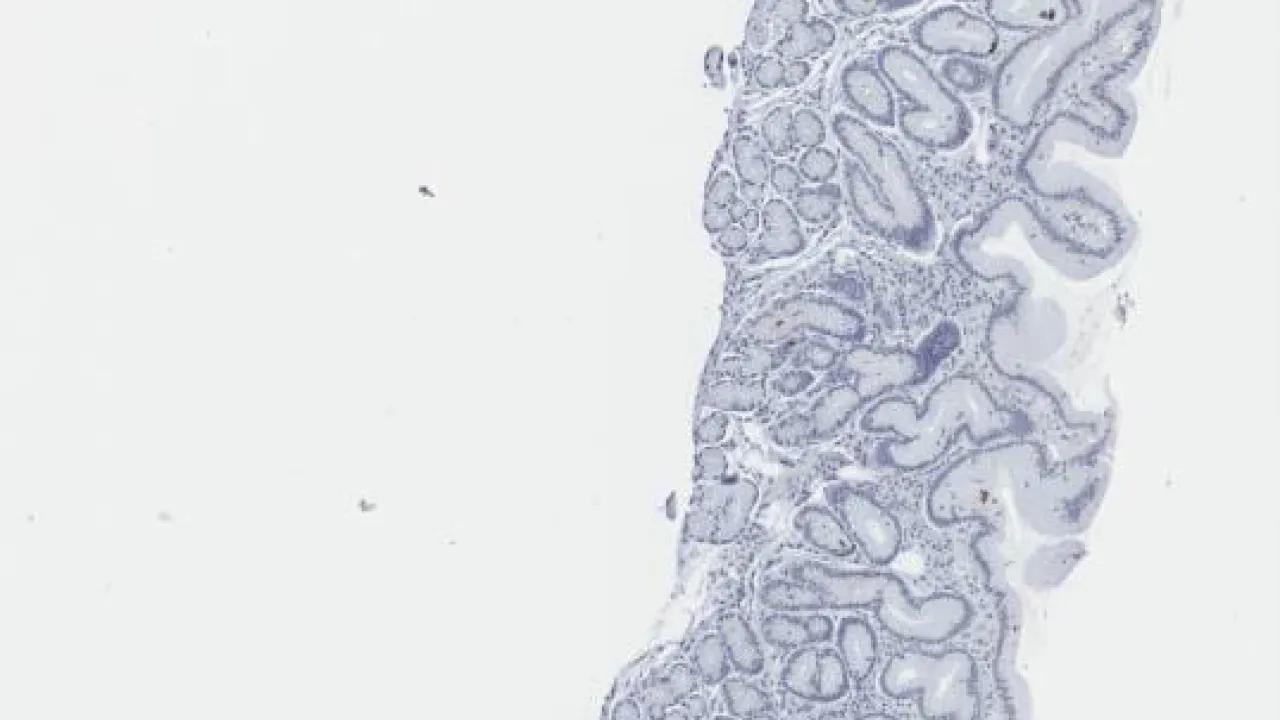

Duodenum, giardiasis